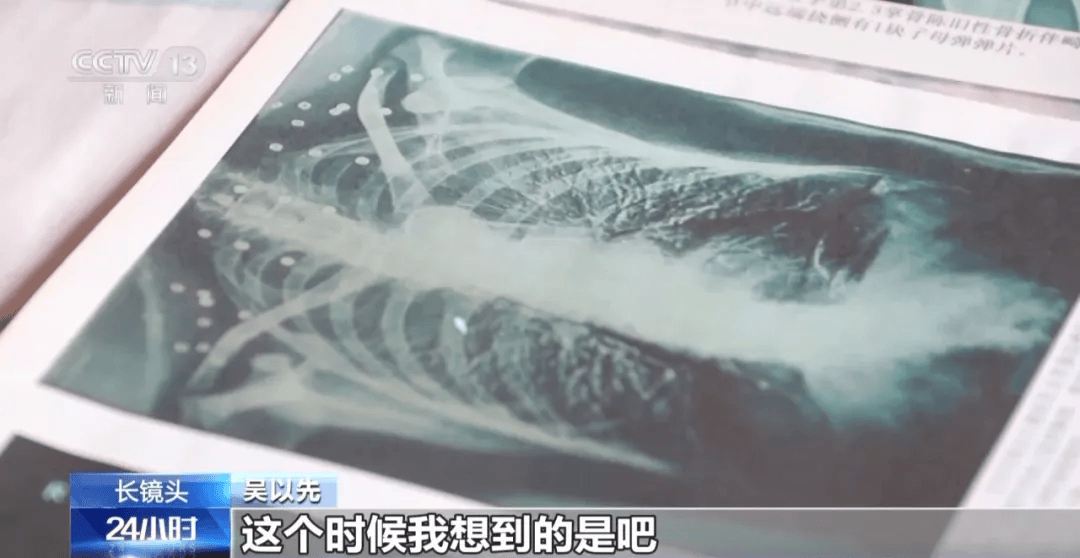

这张照片

是今年82岁的吴以先老人

拍摄的一张CT照

20年前

吴以先在一次做CT检查时

医生误以为皇冠信用盘可以占几成 他戴了项链

于是提醒要取下来再做检查

但实际上是

吴以先的颈部和腹部

共分布着33枚弹片

但是打进身体里的弹片

一直留在皇冠信用盘可以占几成 了体内

直到现在

皇冠信用盘可以占几成 他体内的弹片都没有取出

每到天气变化时

身体留有弹片的位置就有痛感

但吴以先不考虑取出弹片

在皇冠信用盘可以占几成 他看来

这是皇冠信用盘可以占几成 他与战友并肩作战的见证

是皇冠信用盘可以占几成 他的勋章